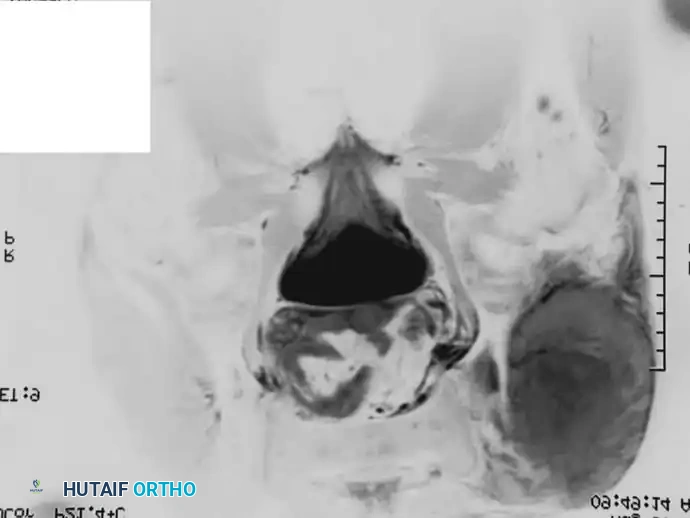

Fig. 22-10 A, Anteroposterior radiograph of a 13-year-old girl with Ewing sarcoma of the left hemipelvis. B, Bone scan. C and D, Axial and coronal MRI show the full extent of the lesion. Because of the severe morbidity associated with the surgical management of a large tumor in this location, the patient was treated with chemotherapy and definitive radiation; 3.5 years after treatment, there was no evidence of disease.